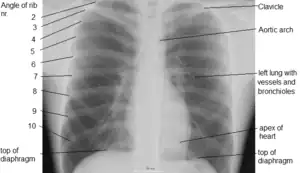

Thorax

Human thorax

Structure

In humans and other hominids, the thorax is the chest region of the body between the neck and the abdomen, along with its internal organs and other contents. It is mostly protected and supported by the rib cage, spine, and shoulder girdle.

Contents

The contents of the thorax include the heart and lungs (and the thymus gland); the major and minor pectoral muscles, trapezius muscles, and neck muscle; and internal structures such as the diaphragm, the esophagus, the trachea, and a part of the sternum known as the xiphoid process. Arteries and veins are also contained – (aorta, superior vena cava, inferior vena cava and the pulmonary artery); bones (the shoulder socket containing the upper part of the humerus, the scapula, sternum, thoracic portion of the spine, collarbone, and the rib cage and floating ribs).

It consists of the ribs and sternum. The ribs of the thorax are numbered in ascending order from 1–12. 11 and 12 are known as floating ribs because they have no anterior attachment point in particular the cartilage attached to the sternum, as 1 through 7 are, and therefore are termed "floating". Whereas ribs 8 through 10 are termed false ribs as their costal cartilage articulates with the costal cartilage of the rib above. The thorax bones also have the main function of protecting the heart, lungs, and major blood vessels in the thorax area, such as the aorta.

Anatomical landmarks

The anatomy of the chest can also be described through the use of anatomical landmarks. The nipple in the male is situated in front of the fourth rib or a little below; vertically it lies a little external to a line drawn down from the middle of the clavicle; in the female it is not so constant. A little below it the lower limit of the great pectoral muscle is seen running upward and outward to the axilla; in the female this is obscured by the breast, which extends from the second to the sixth rib vertically and from the edge of the sternum to the mid-axillary line laterally. The female nipple is surrounded for half an inch by a more or less pigmented disc, the areola. The apex of a normal heart is in the fifth left intercostal space, three and a half inches from the mid-line.